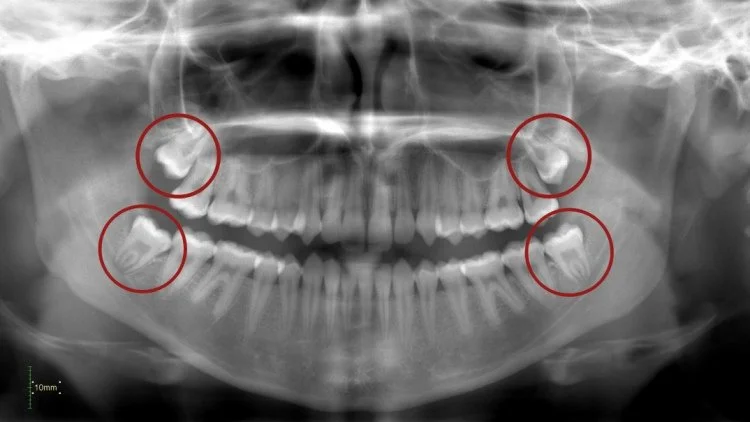

Pour ce faire, nous réalisons des radiographies (si nécessaire), des photos couleur et toujours des modèles numériques 3D de votre dentition. Nous examinons vos dents, vos gencives et vos muqueuses afin de détecter à temps toute anomalie ou maladie. Nous vérifions également la couleur et la position de vos dents.

X10 (2x) : petites radiographies (sur indication)

X21 : radiographie grand format (sur indication)